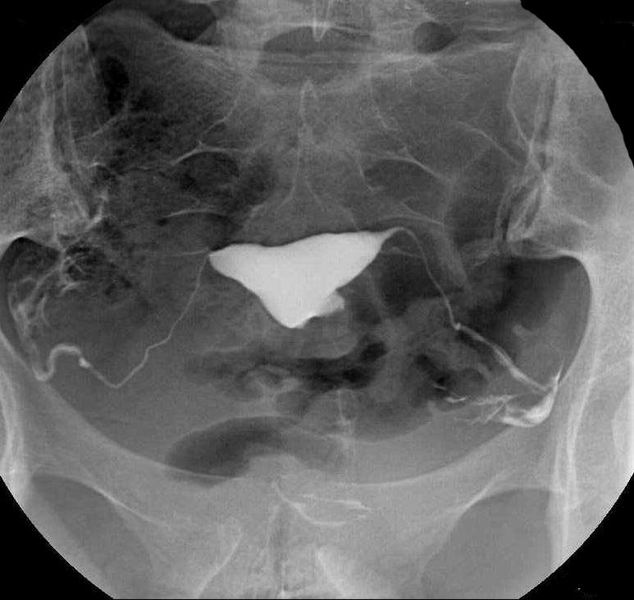

Hystero-salpingografie